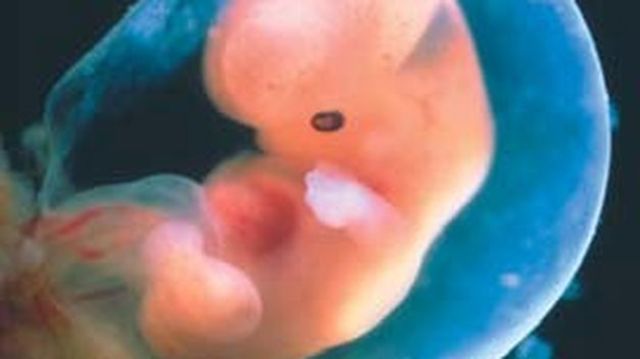

Se forma la estructura básica del cuerpo. Principia e desarrollo de los ojos, de los oídos, de la boca y la nariz. Se observan los brotes que van a dar origen a los brazos y a las piernas. La prominencia cardíaca en muy visible. Se desarrollan las vesículas cerebrales.

• Semana 6 y 7

Semana 6 y 7

Progresa el desarrollo de la tráquea, la laringe y los bronquios. La cavidad oral y la nasal comienzan a separarse, se forma el paladar. Se desarrollan más las piernas y los brazos que parecen aletas.